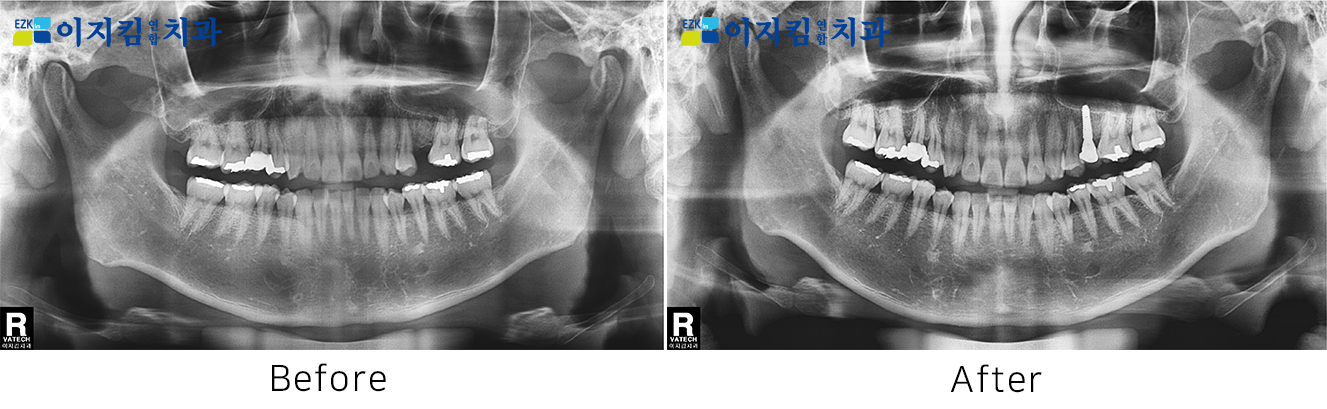

ÀÓÇöõÆ® Àü ¡¤ ÈÄ »çÁø

[

Á¶È¸¼ö : 3425

]